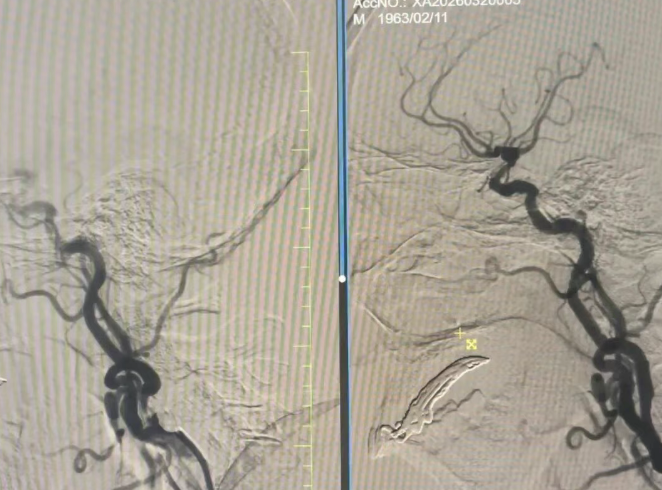

了解刘大爷的病史和求医经历后,神经内科团队高度重视,第一时间组织医护团队会诊,结合各项检查结果反复研讨、详细评估,最终制定了精准个性化的治疗方案——脑保护伞下右侧颈内动脉支架置入术。该手术难度较高,对医护团队的技术水平和配合默契度要求极高。

手术当天,医护团队默契配合、精准操作,每一个动作都严谨细致、行云流水。凭借丰富的临床经验和精湛的医疗技术,原本复杂的手术仅用30分钟便顺利完成,全程出血少、创伤小,最大限度降低了手术风险。